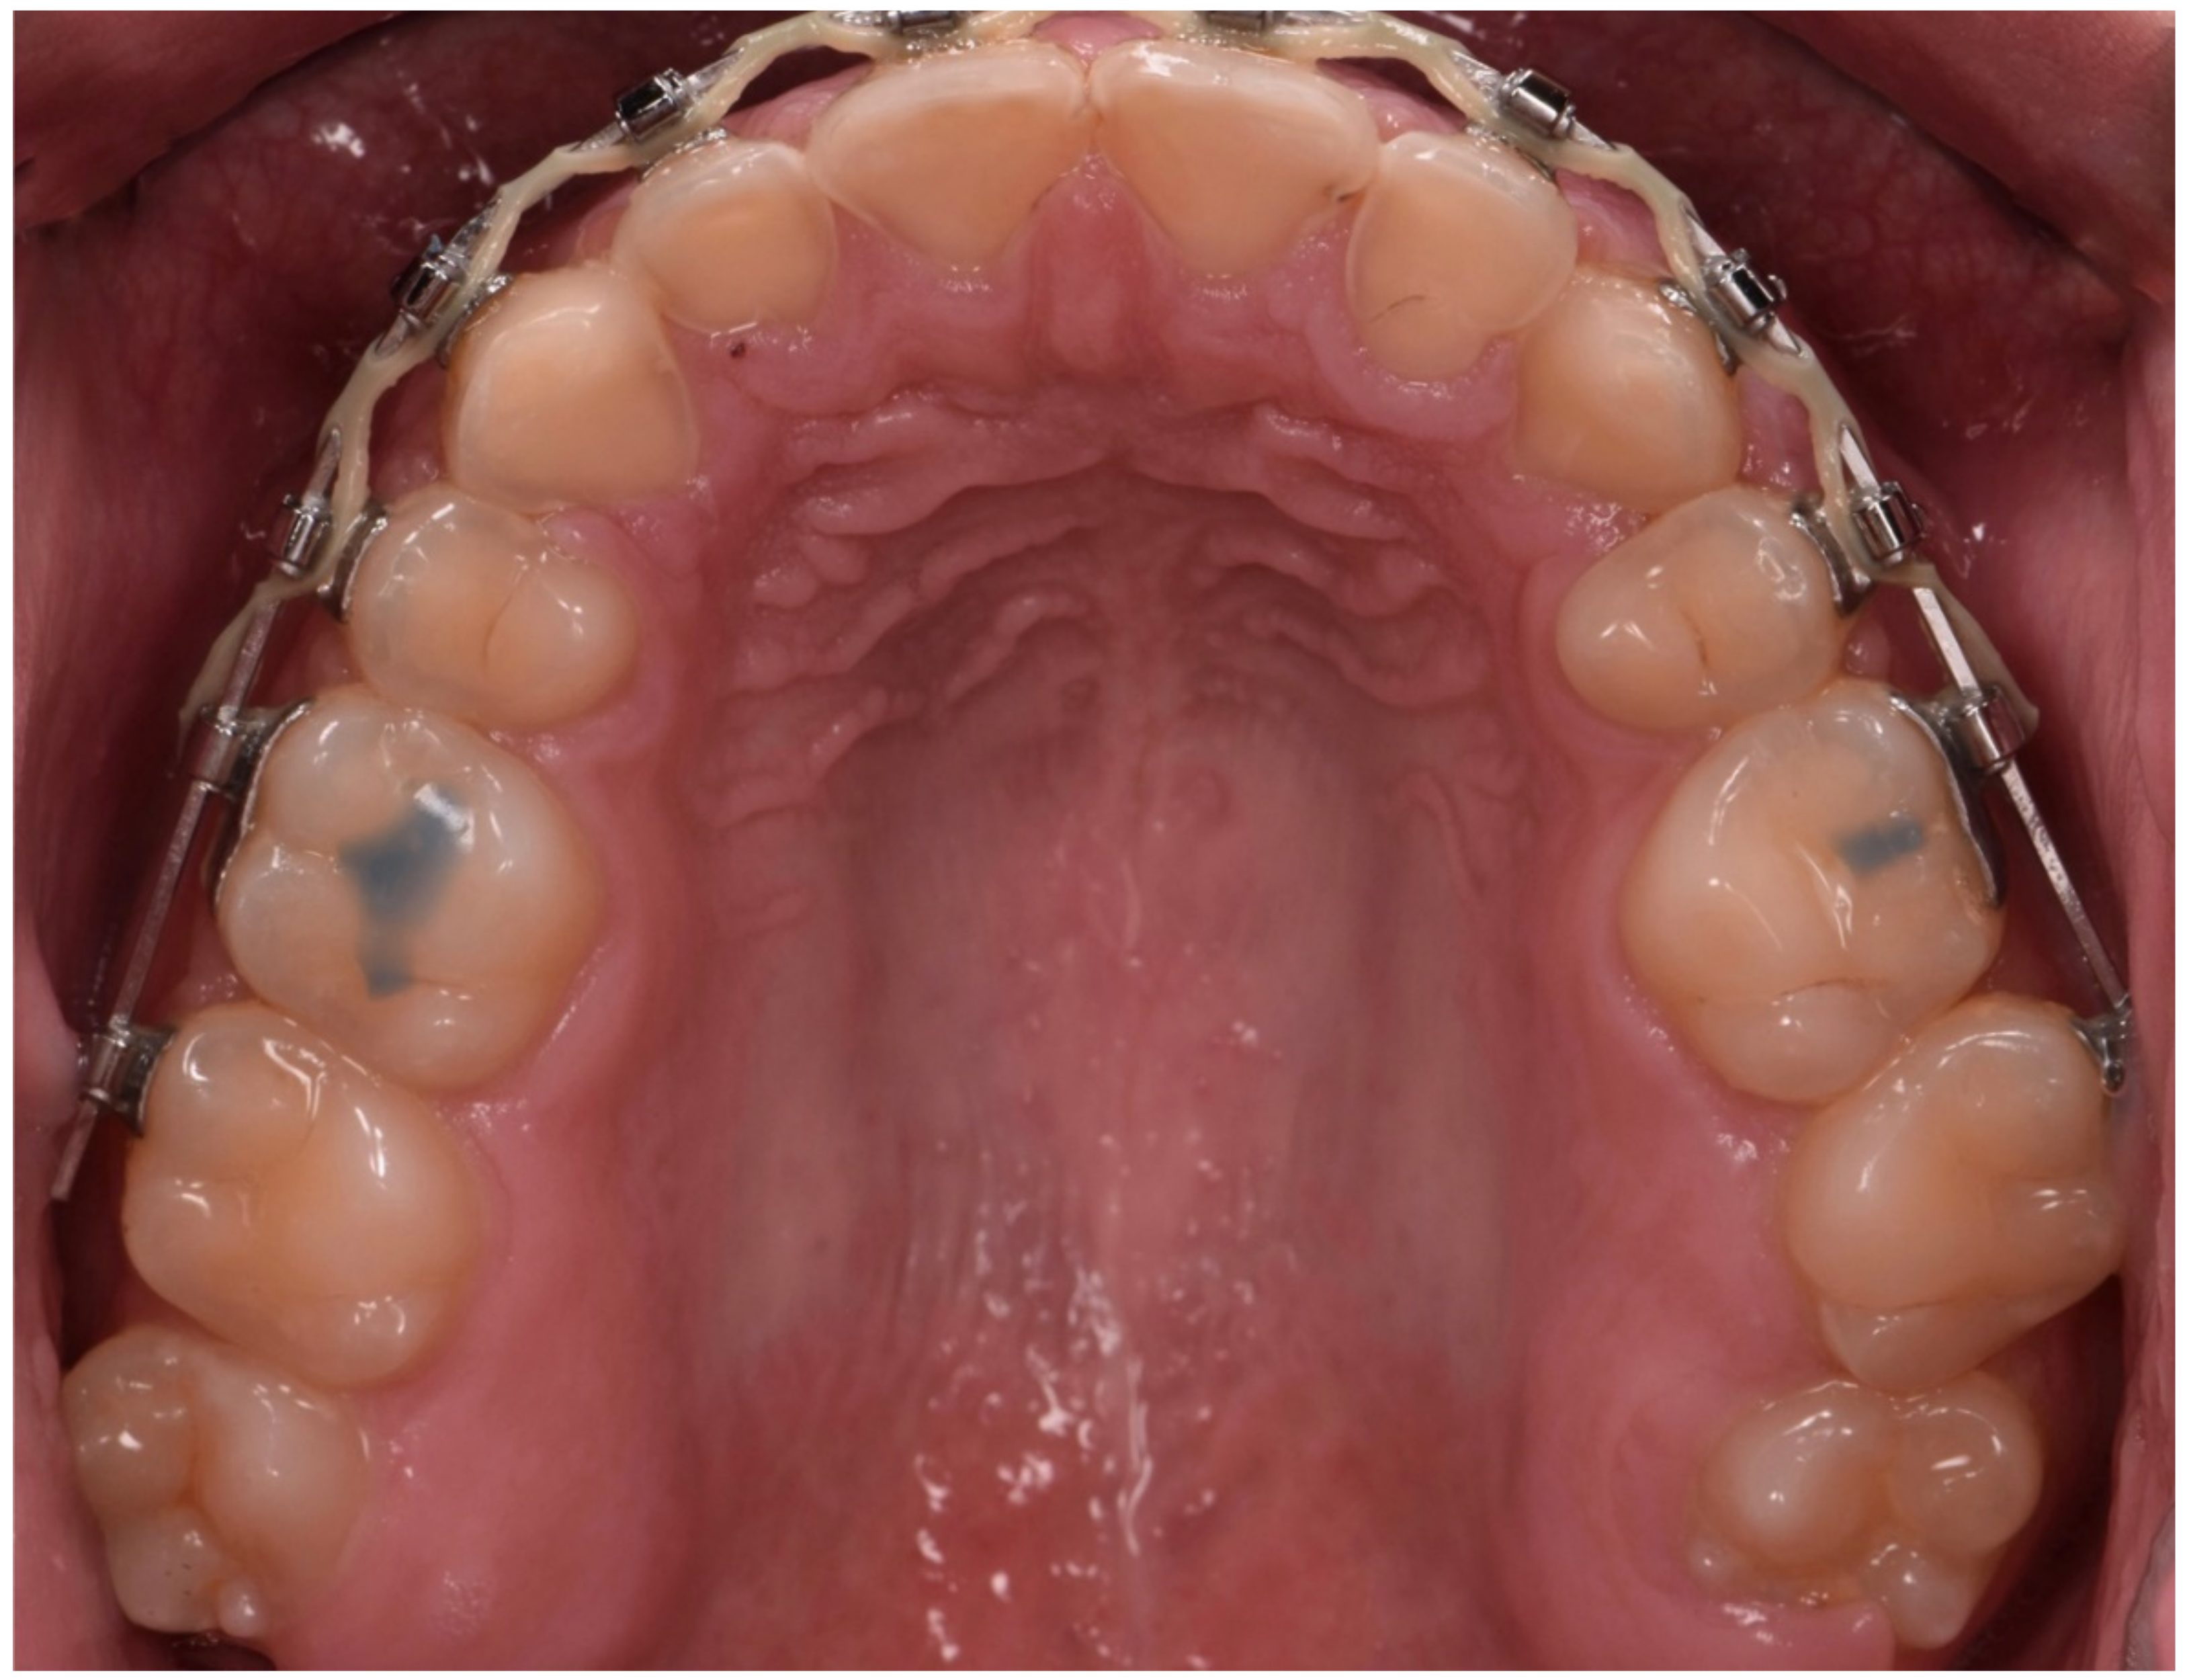

2.2. Restorative Phase